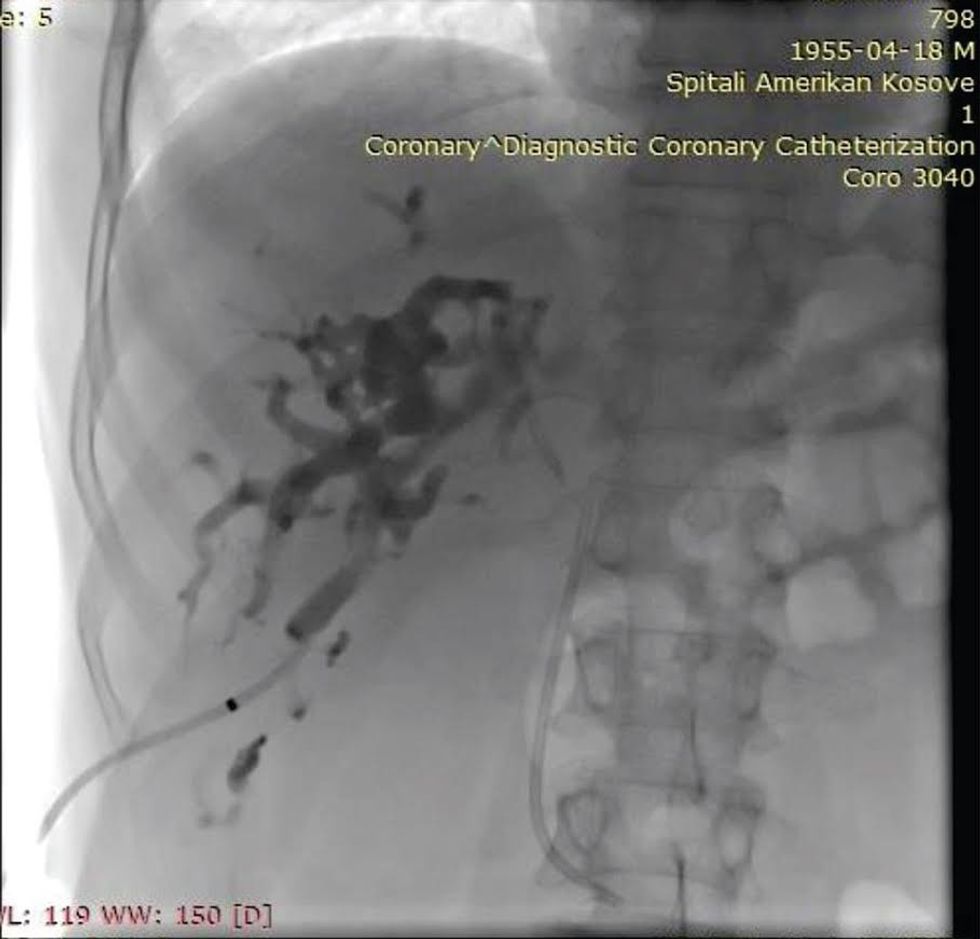

Kolangiografia Perkutane Transhepatike me drenim të rrugëve biliare (PTC) është një teknike e Radiologjisë Invazive nëpërmjet së cilës realizohet fillimisht akcesi dhe më pas drenimi i rrugëve biliare në rastet e obstruksionit të koledokut ose rrugëve biliare qendrore.

PTC-ja si procedurë pikërisht këtë gjë synon, largimin e sekrecioneve biliare prej trupit të pacientit në rastet kur ka bllokim përgjatë rrjedhjes së tyre natyrale.